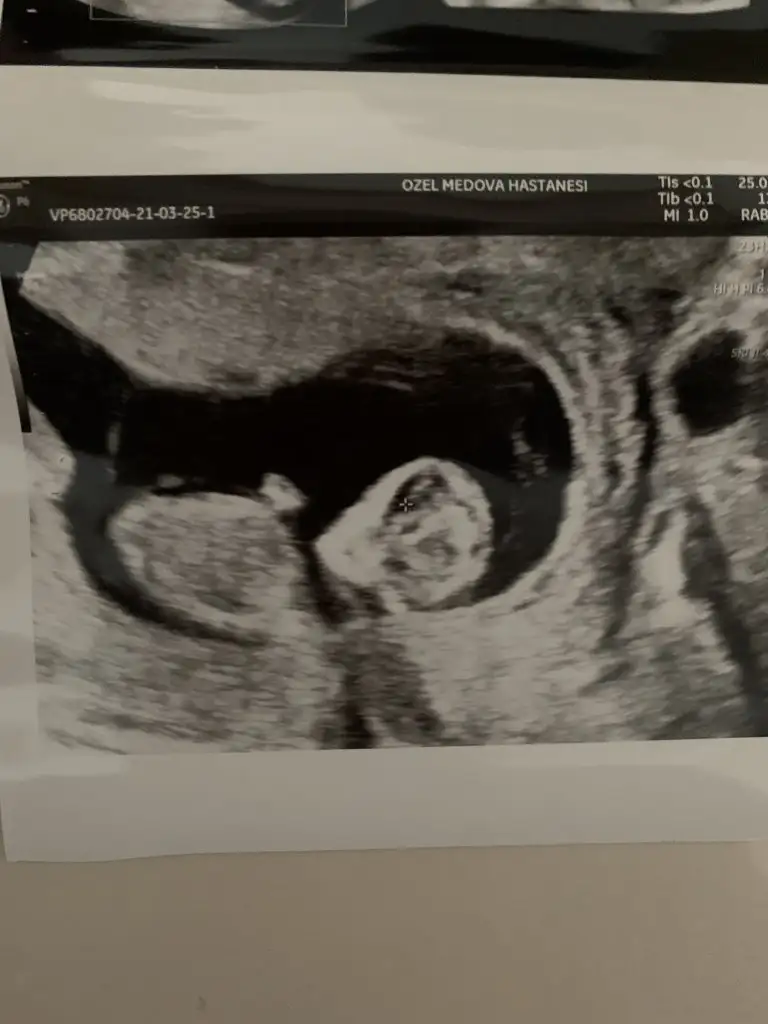

Çok sağol canım yaa çok erken dedi 11+4😁 bir hayli hareketliydi usg çıktısı çok iyi değil ama gerçi yukarı koydum bir daha koyayım bir bakın pek tahmin edilemiyor gibi ama 🤭😅